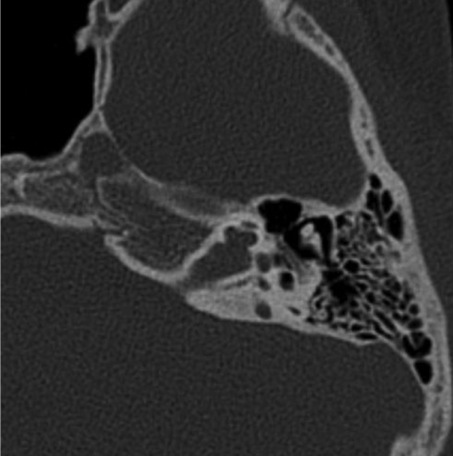

Dehiscence between the basal turn of the cochlea and the lateral end of the internal meatus

Communication between cochlea and lateral internal meatus, isolated or in patients with X LINKED MIXED DEAFNESS. Congenital stapes fixation, suspicious when avascular middle ear and posterior crura abnormality of the stapes.) |